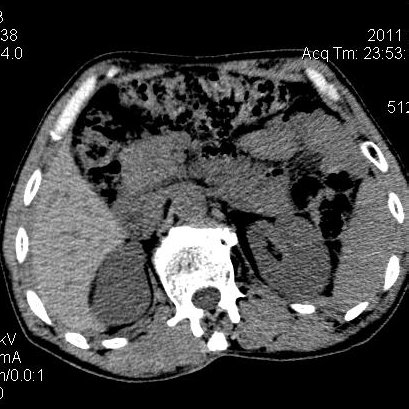

肝左叶发育异常

男性,55岁,骑摩托车摔倒后入院,自述右上腹疼痛

[backcolor=#FF0000]第一次诊断的时候也是这么肯定,可是床旁超声检查并没有发现明显异常,而且患者的一般症状都良好。还好临床只是保守治疗,没有立即手术,第二次复查的时候没有一点变化,又做了MRI检查,没有血肿,

这是一例肝左叶发育异常的,很个性吧~[/backcolor]